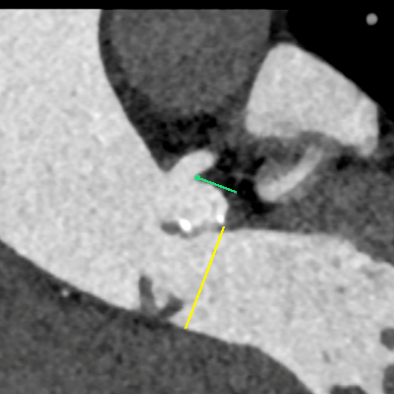

CT测量

主动脉根部CT测量

瓣环周长:68.1mm

最长直径:23.3mm

LVOT周长:69.0mm

最长直径:23.8mm

左冠开口高度:8.7mm

右冠开口高度:8.4mm